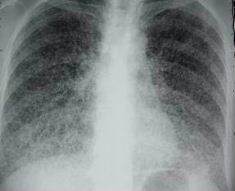

AEG, fièvre, parfois sueurs nocturnes. Patient vivant dans un squat.

Milaire tuberculeuse